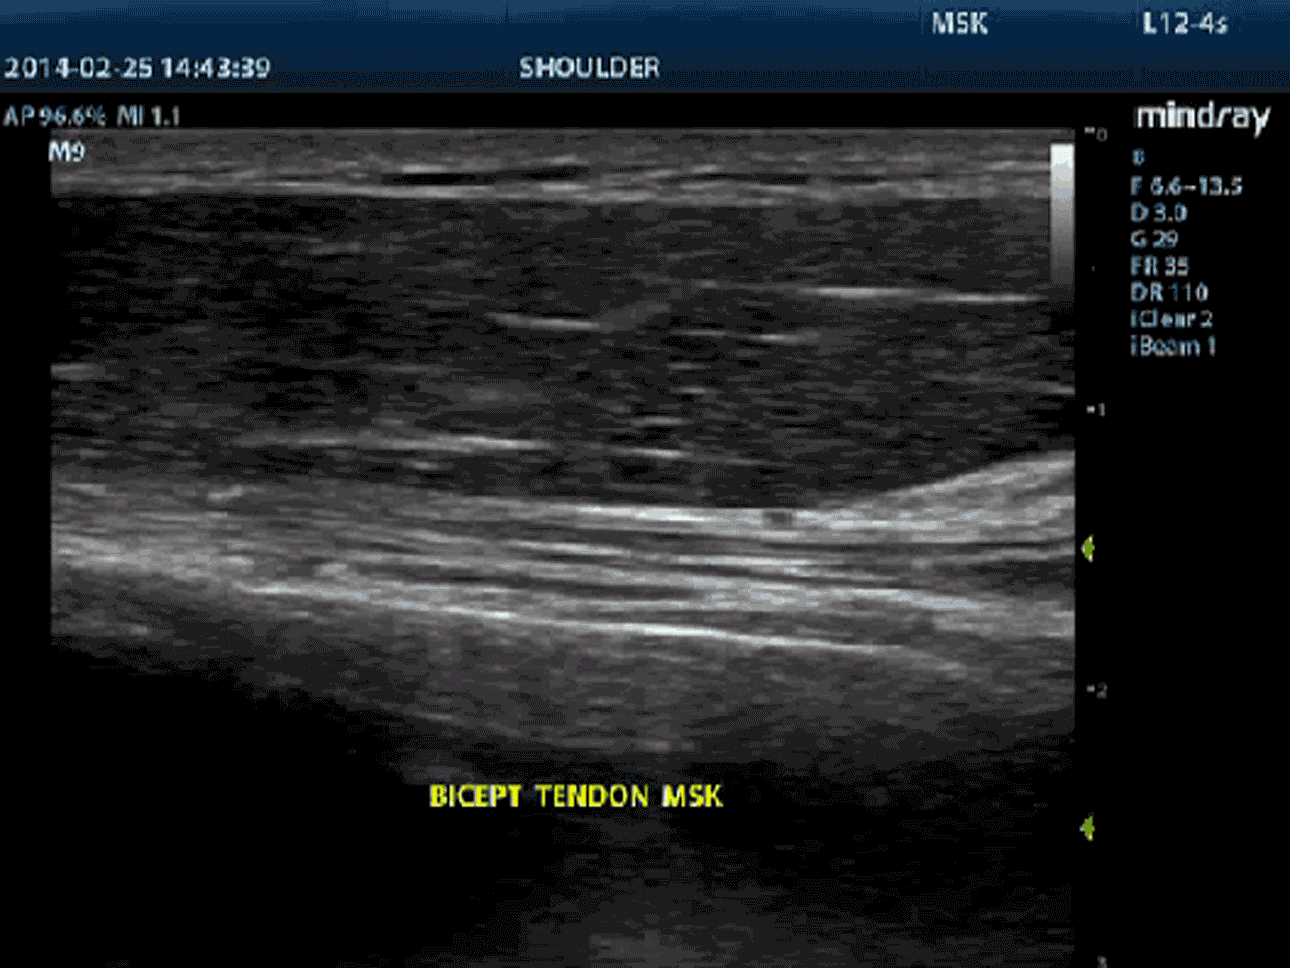

Zaawansowane elementy do przesyłania i odbierania sygnału zapewniają wysoką czułość i dokładność wykrywania echa. Innowacyjne technologie zastosowane w sondach pozwalają na lepszą penetrację i wyższą rozdzielczość, co znacznie poprawia możliwości diagnostyczne.

iBeam™ (obrazowanie krzyżowe)

Funkcja ta pozwala wykorzystywać skany wykonane pod różnymi kątami do stworzenia pojedynczego obrazu, co daje wzmocnienie rozdzielczości, kontrastu i lepszą wizualizację.